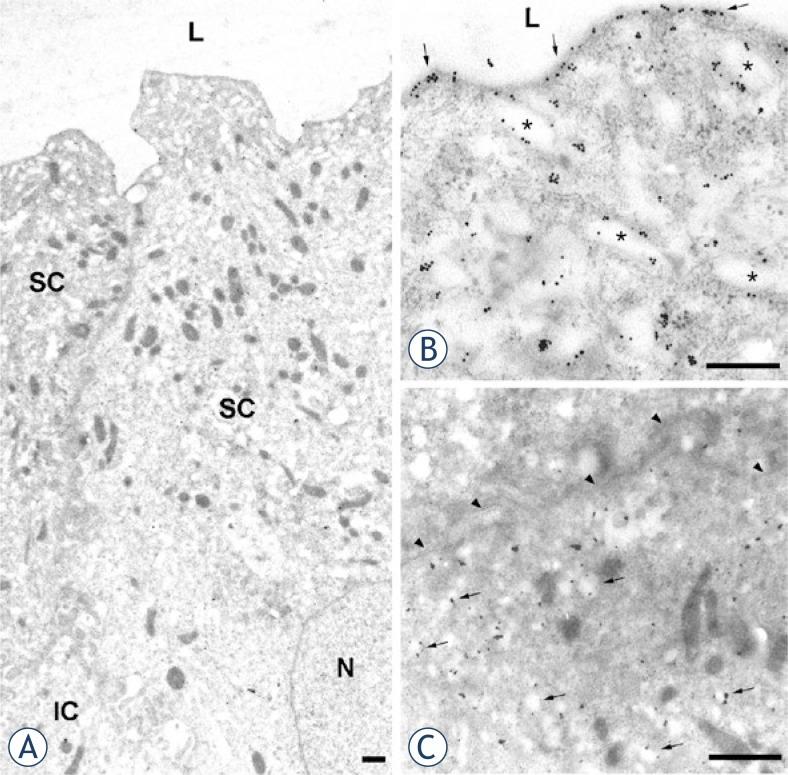

Uroplakins are differentiation-related membrane proteins of urothelium. We compared uroplakin expression and ultrastructural localization in human normal urothelium, papilloma and papillary carcinoma. Because of high recurrence rate of these tumours, treated by transurethral resection, we investigated urothelial tumour, resection border and uninvolved urothelium.

Urinary bladder samples were obtained from tumour free control subjects and patients with papilloma and papillary carcinoma. Immunohistochemical and immunoelectron labelling of uroplakins were performed.

In normal human urothelium with continuous uroplakin-positive superficial cell layer uroplakins were localized to flattened mature fusiform vesicles and apical plasma membrane of umbrella cells. Diverse uroplakin expression was found in papilloma and papillary carcinoma. Three aberrant differentiation stages of urothelial cells, not found in normal urothelium, were recognized in tumours. Diverse uroplakin expression and aberrant differentiation were occasionally found in resection border and in uninvolved urothelium.

We demonstrated here that uroplakin expression and localization in urothelial tumours is altered when compared to normal urothelium. In patients with papilloma and papillary carcinoma immunolabelling of uroplakins at ultrastructural level shows aberrant urothelial differentiation. It is possible that aberrant differentiation stages of urothelial cells in resection border and in uninvolved urothelium contribute to high recurrence rate.